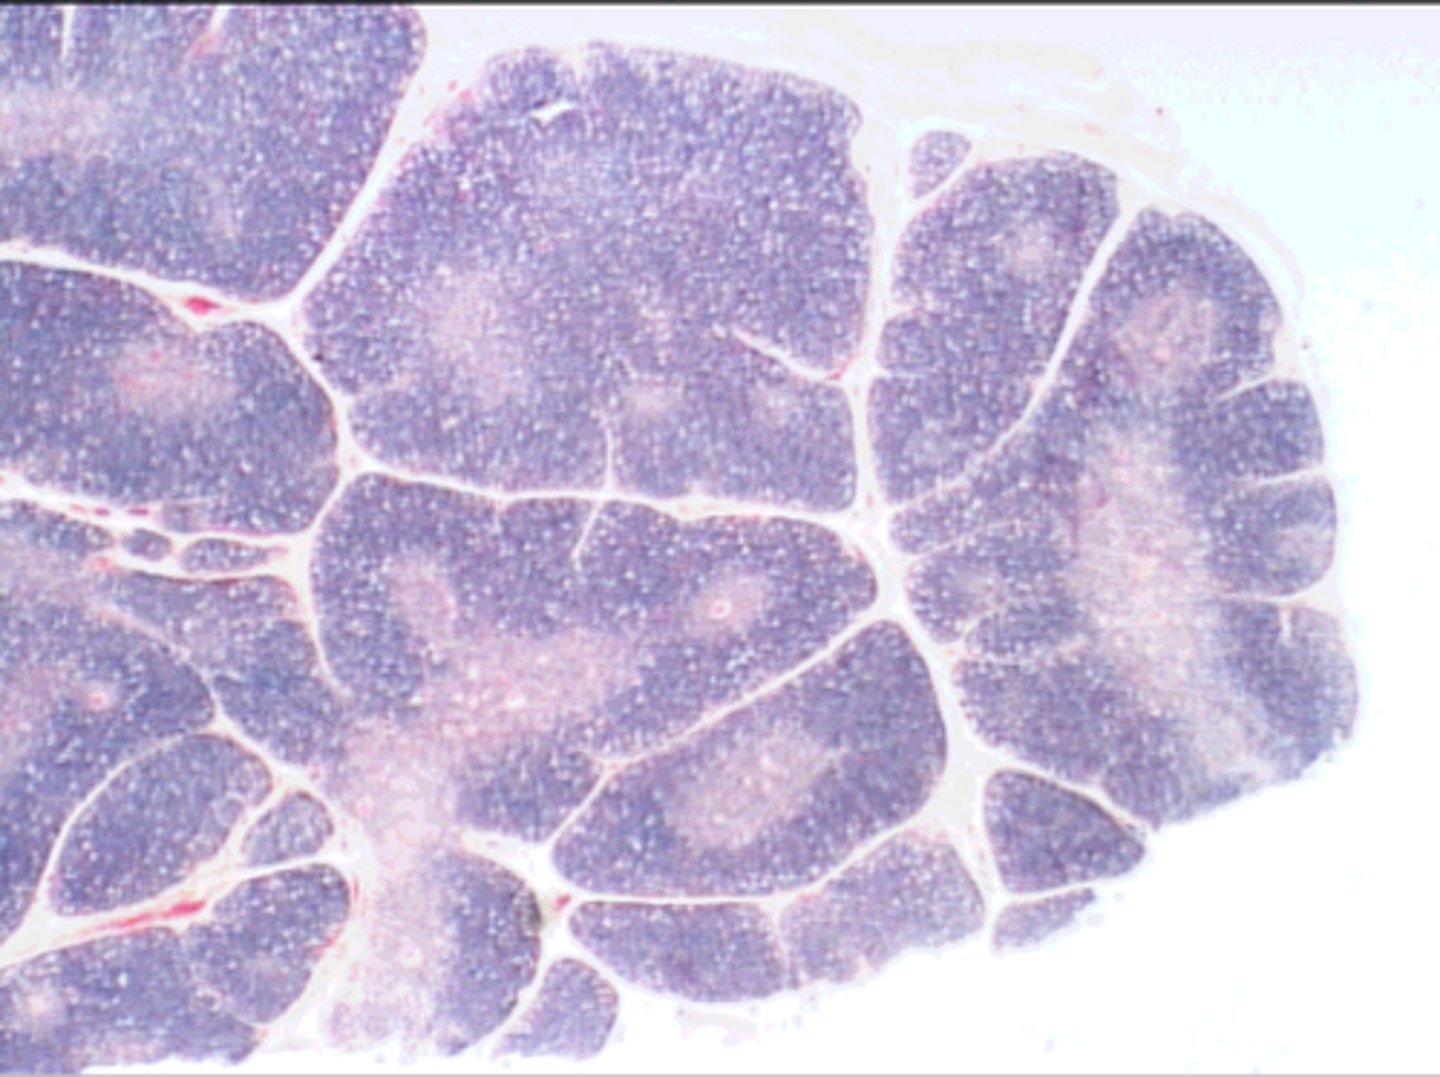

Peyer's patches in ileum

collection of secondary lymphatic nodules

ID structure

Peyer's patches

black arrow